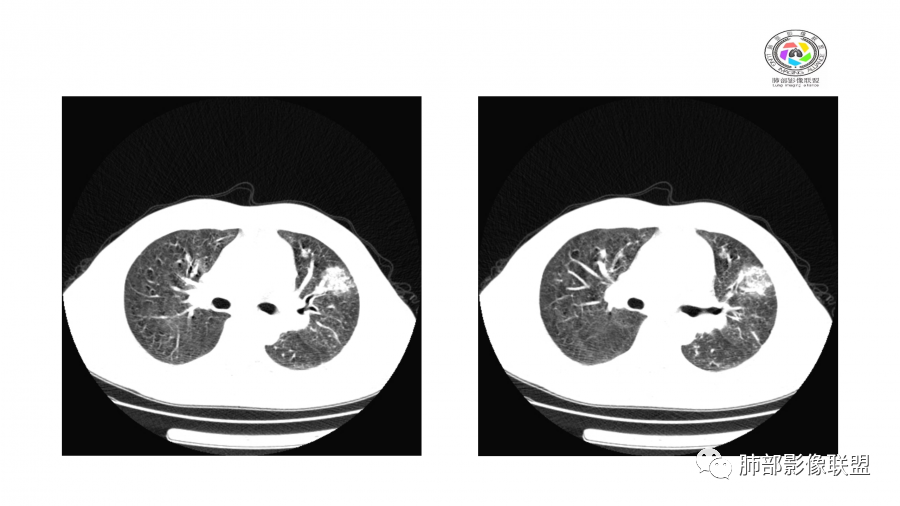

患者,男,49岁,初次以头晕呕吐肾功能异常入院,后期伴双下肢水肿,CT示双肺多发斑片及结节影,部分周围伴晕,部分内部可见支气管穿行,多次复查可见部分病灶略吸收及新发病灶出现,最后一次复查双肺多发磨玻璃样改变,综合考虑血管炎,最后一次伴肺水肿可能

中年男性,高血压,肾功能衰竭,贫血病史,尿潜血阳性。3.8双肺野多发斑片磨玻璃实变影,结节影,边缘模糊,周围有晕征,内见支气管充气征,主要沿支气管血管束分布,部分胸膜下分布,3.12号病灶有吸收好转,4.8号斑片实变影基本吸收,主要沿支气管血管束分布结节影,边缘平直收缩,4.28病灶大部分吸收好转,双肺支气管血管束增粗,有少量结节影。考虑ANCA相关性血管炎可能性大,第一次片子觉得隐球菌不排除,但是后面没有抗真菌治疗就吸收了,觉得隐球菌可能性不大。

胸部CT:双肺多发实性斑片影,散在GGO。实性斑片周围可见晕征、边缘模糊不清,病灶于肺外围区域优势分布。肺门区血管影增粗,支气管套袖,目测肺动脉增粗。3月、4月复查肺内实性斑片病灶呈游走性,此起彼伏。

王秀仙:

双肺多发斑片及结节状磨玻璃影,部分内部可见支气管穿行,多次复查可见部分病灶略吸收及新发病灶出现,肾功能不全,贫血,综合考虑肺泡出血,血管炎。

谢加平:

双肺多发斑片影,沿支气管血束分布,前后复查对比,大部分有吸收好转,另外新发(此起彼伏特点),患者肾功能不全及肾性高血压,首选血管炎,并肺泡出血可能。